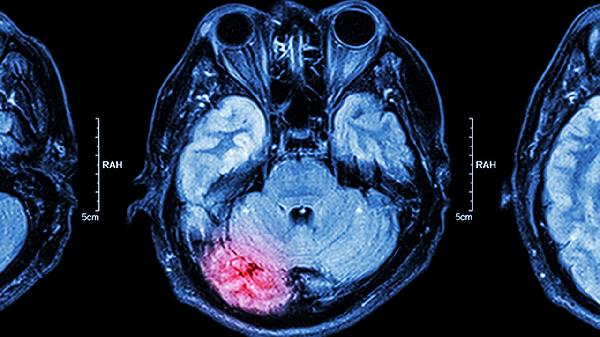

3、脑血栓后遗症

脑血栓形成后遗留肢体麻木、言语不利等后遗症时,该药辅助治疗可促进神经功能恢复。其机制与增加缺血区脑血流、保护神经细胞有关。急性期过后3-6个月恢复期使用效果较显著,但需排除脑出血等禁忌证后使用。